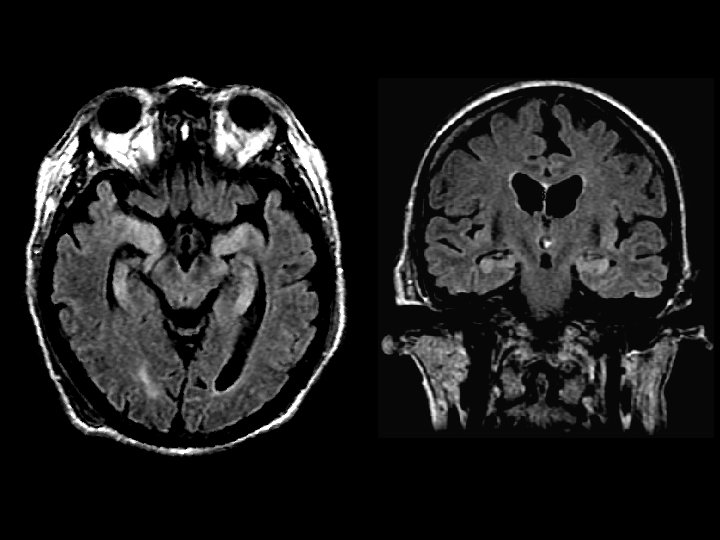

Herpes Encephalitis • Findings – Bilateral temporal lobe FLAIR signal (postseizure edema) • HSV 2 in neonates • HSV 1 in adults – latent infection in the Gasserian ganglion (CN V) – predilection for the limbic syste, cingulate gyrus, and subfrontal region – late stage becomes bilateral, hemorrhage